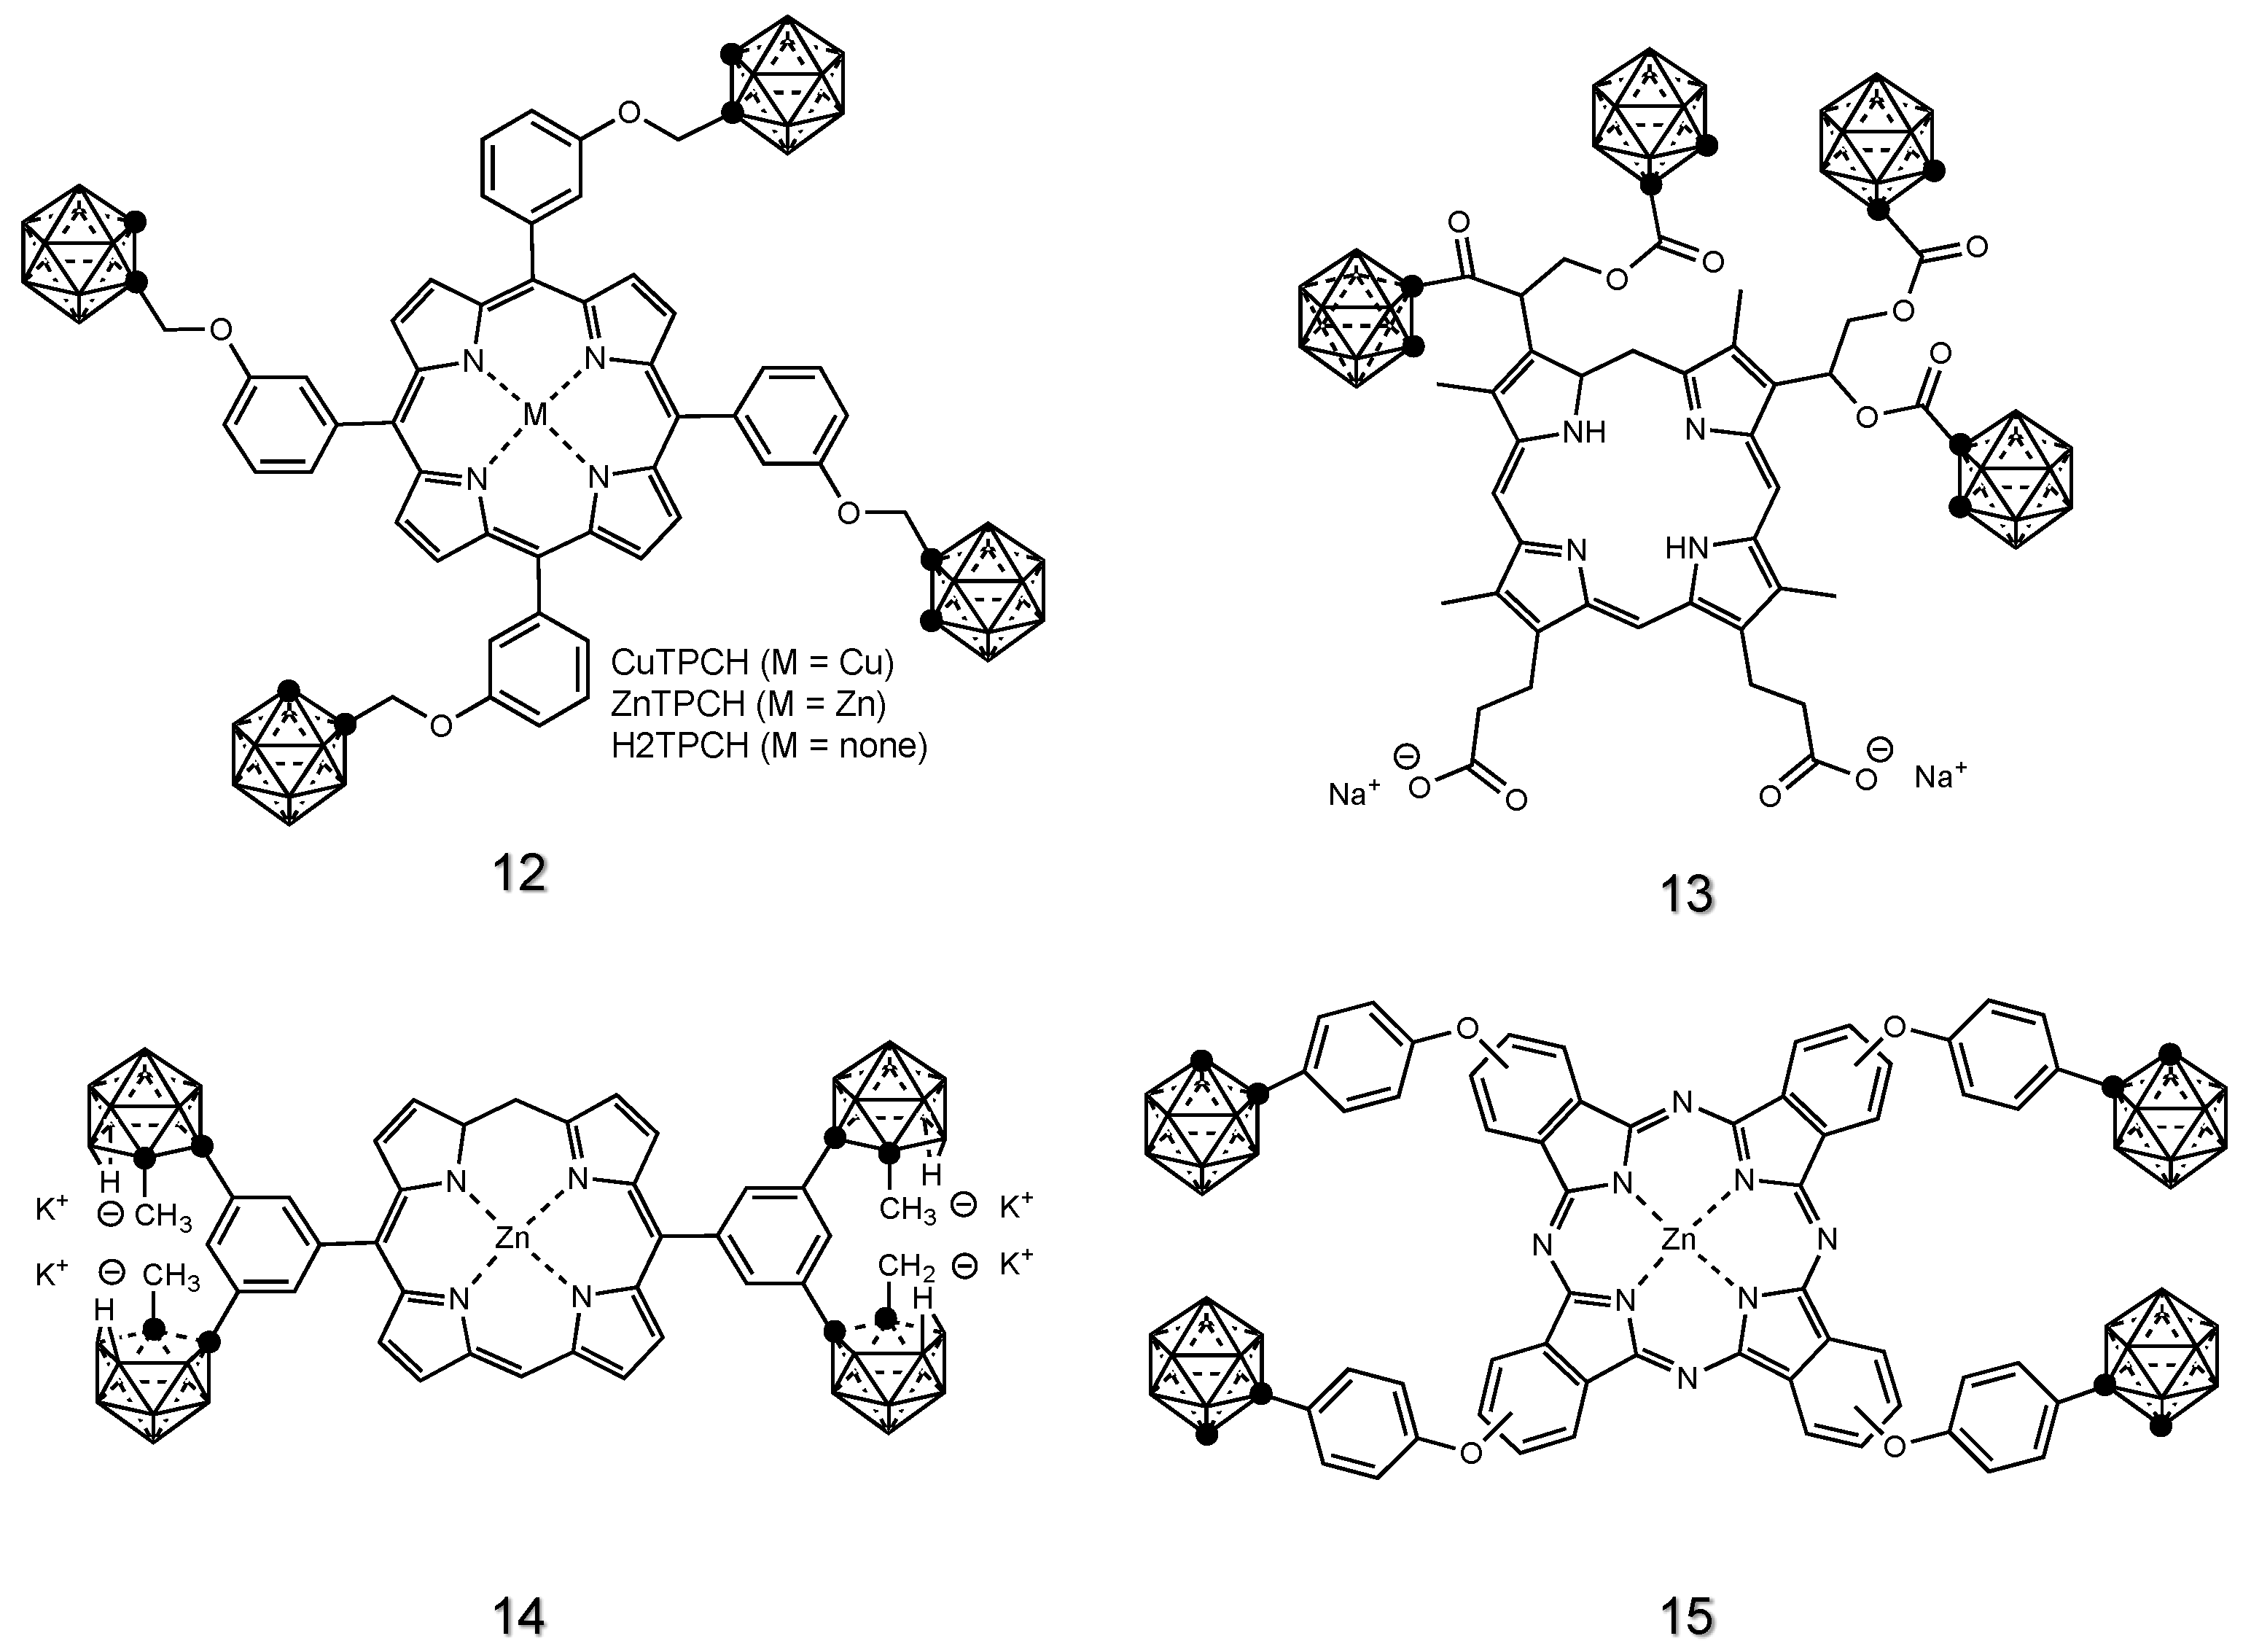

2.1.4. Porphyrin Derivatives of Carboranes